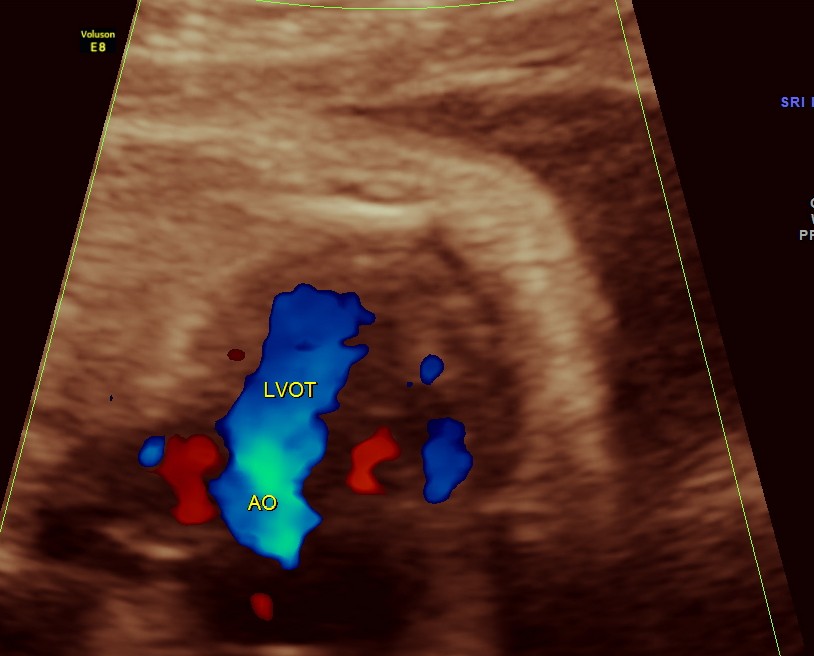

The next 2 images show the findings of the fetal heart. Significant hypertrophy of the septal and apical regions of the Left ventricle are seen.